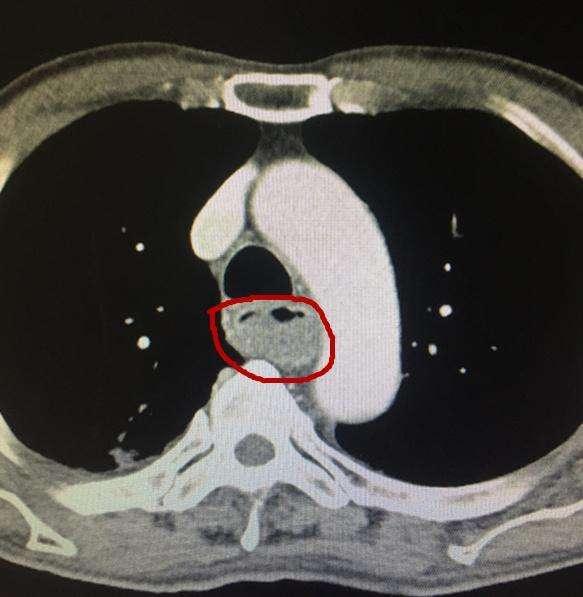

(2)心脏大血管

肺部CT可以看心脏结构有没有问题,心脏大不大,心肌厚不厚,有没有室壁瘤,大血管,肺动脉,主动脉有没有异常,有没有血管瘤,动脉夹层,动脉硬化等等。专门的冠状动脉CT,还可以看供应心脏的冠状动脉有没有粥样硬化,有没有动脉狭窄,狭窄的严重程度,也就是判断有没有冠心病,需不需要放置冠脉支架。冠状动脉的CT可以部分替代冠脉造影检查。

冠脉CT